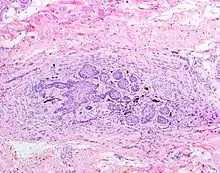

The juxtaoral organ of Chievitz is composed of nests of benign squamoid epithelium closely associated with multiple nerve bundles. The deep location and squamous appearance can histologically mimic invasive squamous cell carcinoma. (Hematoxylin and Eosin stained section, 100x magnification)

The juxtaoral organ in humans is a small longish structure (10–14  mm in length, 1–2  mm in diameter), situated medially to the medial pterygoid muscle. The organ consists of a central ramified cord of epithelial parenchyma, embedded in connective tissue particularly rich in nerve fibers and sensory receptors. Close relations exist between epithelial cells and nerve endings. Histochemically, the parenchyma displays a characteristic pattern of various enzymes. Sporadically, epithelial follicles containing colloidal material can be found. The organ is surrounded by a dense, perineurium-like connective tissue.